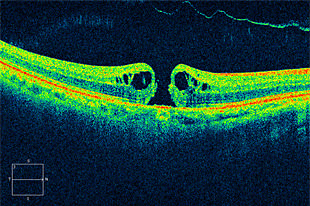

黄斑円孔

網膜の中心である黄斑部に穴が開く病気で、視野の中央が見えにくくなります。

術前写真

術前 OCT

術後写真

術後 OCT